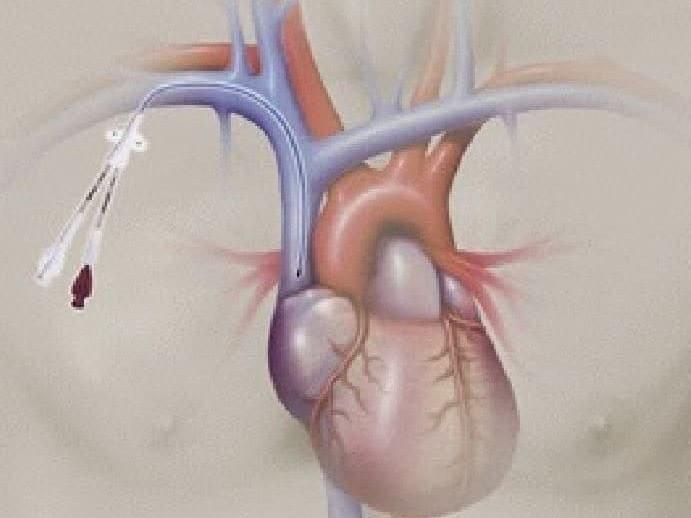

Miniature Doppler probe can be inserted via the distal lumen and easily positioned directly into the venous blood flow.

Compare the left side picture with the one on the right side

Getting both left-sided and right-sided perspective helps to discern better false positivity or false negativity of other monitoring methods used in hemodynamic therapeutical management.